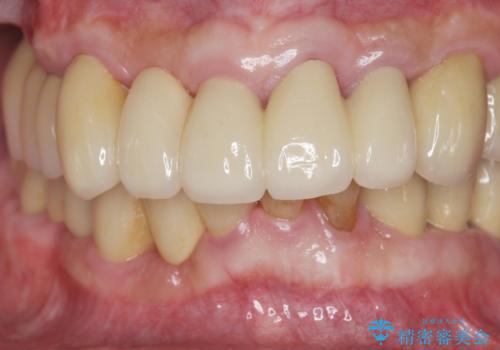

歯周病治療を伴う前歯審美セラミック治療

歯周外科を行ったことで非常に安定した歯周環境となり、引き締まった歯ぐきとなりました。